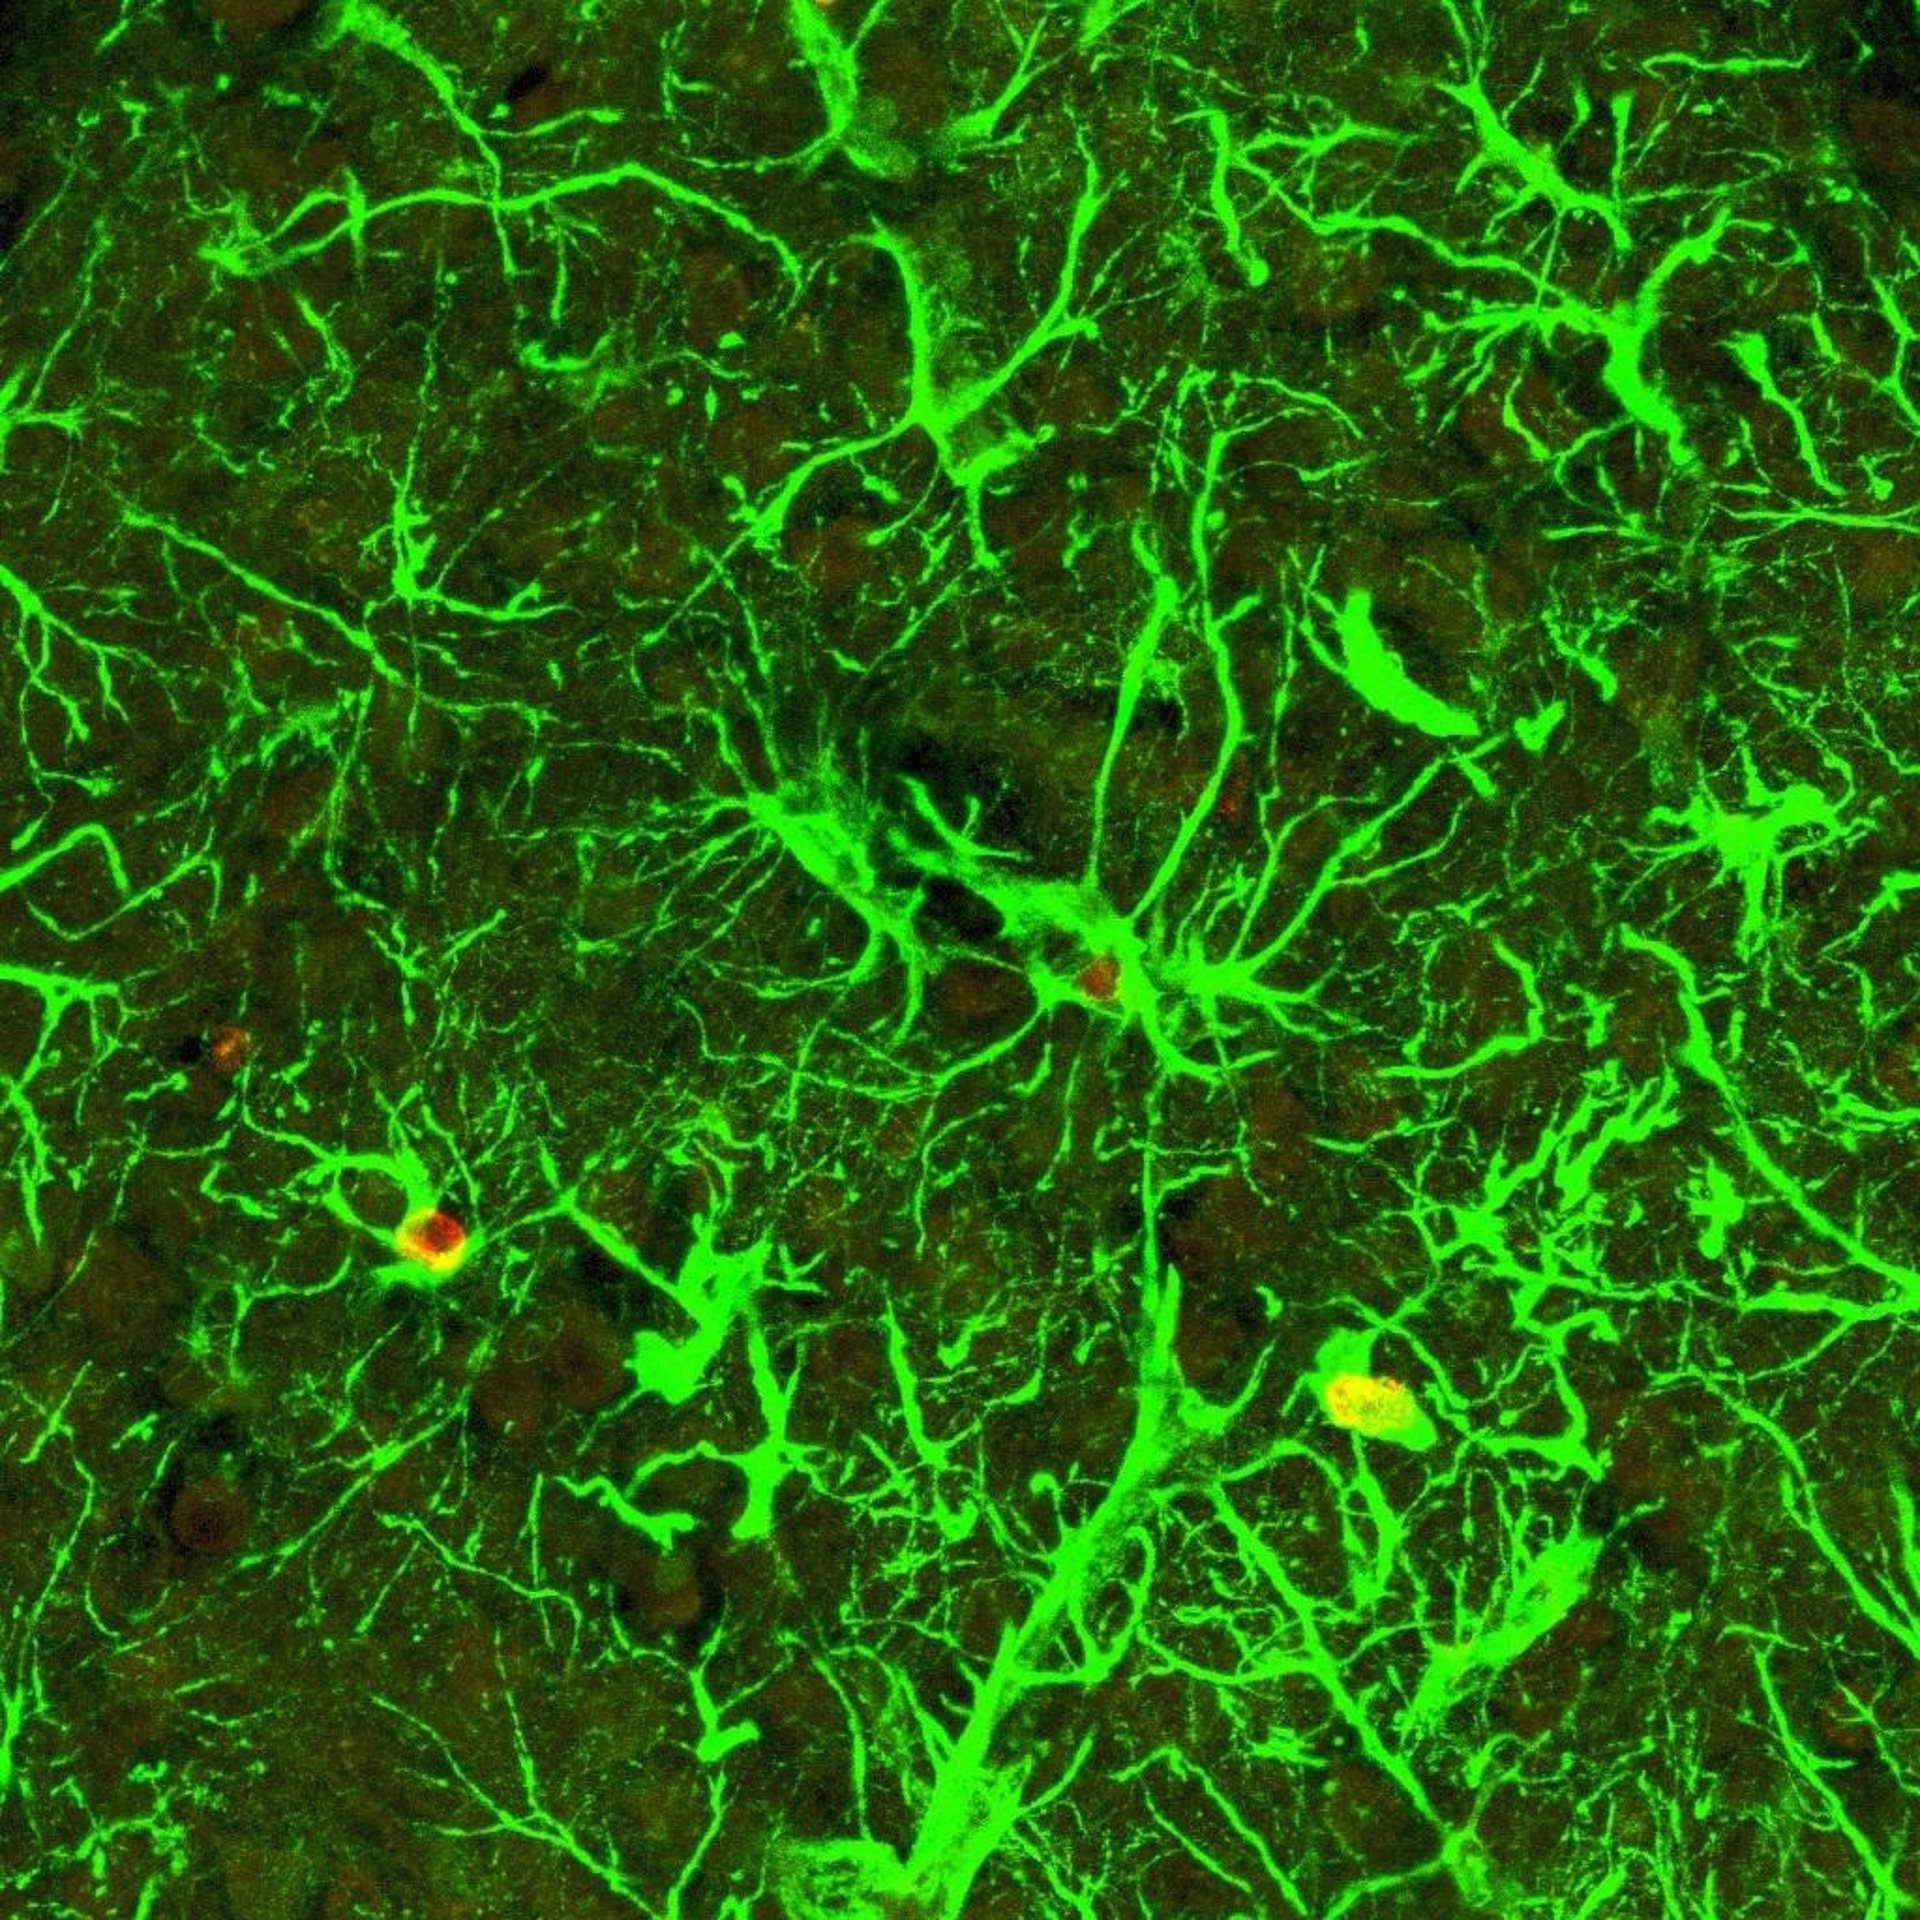

Astrocitos

Por el momento, ha explicado Gangoso en declaraciones a DiCYT, recogidas por Europa Press, ya se ha logrado disminuir la proliferación de estas células aumentando los niveles de expresión de conexina 43, una proteína "muy importante en la comunicación de los astrocitos, células del sistema nervioso central".

Esto puede resultar clave ya que una de las características de los gliomas es que no tienen comunicación entre las células gliales o astrocitos, y lo que hace la conexina 43 es aumentar la comunicación entre estas células y parece que esta es la vía que inhibe la activación del oncogén. De hecho, "cuanto más maligno es un tumor, menor es la expresión de conexina 43", ha comentado Gangoso.